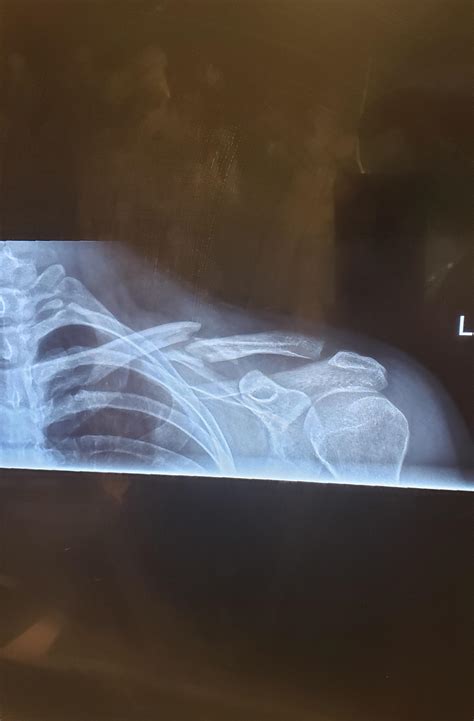

This is my collarbone after I dove for a football and landed on the ...